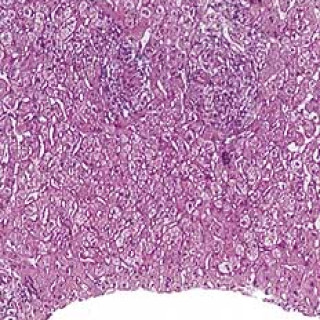

Svulster i hjertet forekomme meget sjelden og kun hos 0,002 – 0,03 % av uselekterte pasienter i store obduksjonsmaterialer (1, 2). Ved Sintef Unimed, Norsk pasientregister, ble det i tiårsperioden 1990 – 99 registrert 82 pasienter med godartet svulst i hjertet, mens det i Kreftregisteret i tiårsperioden 1988 – 97 ble registrert ni pasienter med primær, ondartet svulst i hjertet. Karakteristisk ved tumor cordis er at de fleste (80 – 90 %) svulstene er godartede. Tre firedeler av de benigne tumorformene utgjøres av myksomer, mens resten hovedsakelig består av rabdomyomer, papillære...